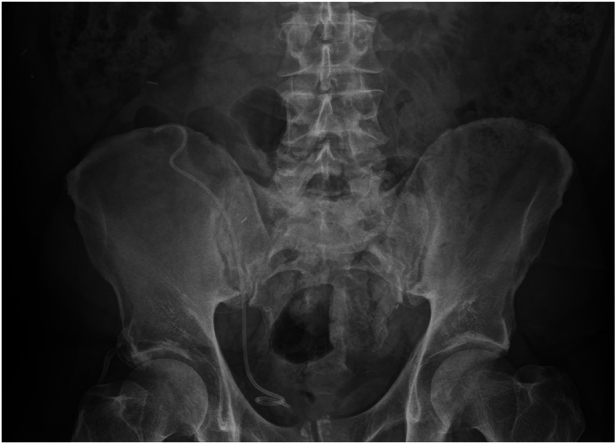

肾移植后,输尿管支架的目的是尽量减少输尿管膀胱吻合术的并发症。虽然移植后没有明确的支架移除时间,但理想的移除时间是 2 到 4 周。然而,被遗忘的支架会对肾移植功能产生不利影响,并导致梗阻性尿病。我们为大家介绍一位保留输尿管支架超过 19 年的 59 岁男性,他的输尿管支架没有包壳、碎裂、移位和结石形成。据我们所知,这是肾移植患者中保留时间最长的输尿管支架,也是第一例在局麻下通过柔性膀胱镜取出的被遗忘的支架。

Following renal transplant, ureteral stents aim to minimise ureteroneocystostomy anastomotic complications. Although there is no specified timing for stent removal after transplantation, these are ideally removed at between 2 and 4 weeks. However, forgotten stents can adversely affect renal allograft function and contribute to obstructive uropathy. We present a 59-year-old man with a retained ureteral stent for more than 19 years with an absence of encrustations, fragmentation, migration and stone formation. To our knowledge, this is the longest retained ureteral stent in a renal transplant patient and the first forgotten stent removed via flexible cystoscopy under local anaesthetic.